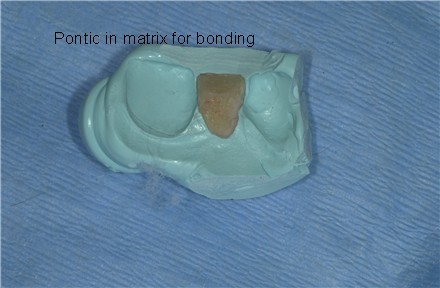

[img]https://www.laserdentistryforum.com/attachments/upload/IMG40c712a8.JPG[/img]

[img]https://www.laserdentistryforum.com/attachments/upload/IMG40c712b5.JPG[/img]

[img]https://www.laserdentistryforum.com/attachments/upload/IMG40c712bd.JPG[/img]

[img]https://www.laserdentistryforum.com/attachments/upload/IMG40c712c5.JPG[/img]

[img]https://www.laserdentistryforum.com/attachments/upload/IMG40c712cf.JPG[/img]DAvid